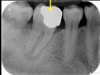

is the following periapical pathology or not?

yes

83

yes - root filled - PDL isnt continuous - lamina dura isnt continuous

84

no

85

86

yes - it is crowned - apical radiolucency - lamina dura tracking off

87

cant tell

88

89

yes - lamina dura tracking off

90

no PDL widened probs cus of brace

91

92